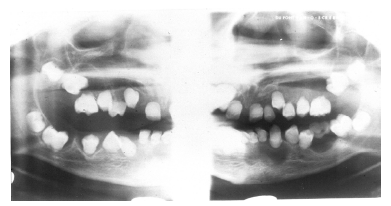

Figure 28 - Congenital Hypodontia

Figure 28

Hypodontia (Too Few Teeth)

Missing teeth is an exceedingly common finding, which can usually be attributed to extraction or traumatic evulsion. Such acquired hypodontia must be contrasted with congenital hypodontia, which arises because of a developmental error.

Congenital hypodontia most commonly affects the third molars, the permanent maxillary lateral incisors and the maxillary and mandibular premolars. Frequently, hypodontia is bilateral. Figure 28 is an example of a patient with congenital hypodontia, affecting the mandibular second premolars bilaterally, the left mandibular first permanent molar, and retention and ankylosis of the mandibular second deciduous molars.